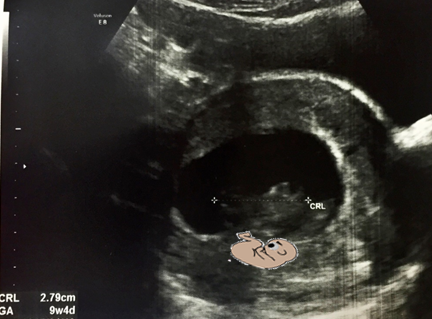

생리가 불규칙한 분들은 조금 더 신경 써서 산부인과 진료를 일찍 보시면, 주수 결정에 도움이 됩니다. 임신 일 분기 때는 보통 CRL(Crown Rump length)을 측정하게 되고, 머리부터 엉덩이까지 길이를 측정하게 됩니다.

3.Crown Rump Length (CRL)

임신 초기에 산부인과 외래를 방문하면 초음파로 임신주수를 정할 때 가장 유용하게 쓰는 CRL입니다. 보통 CRL 은 3번 정도 측정해서 평균값을 구하며, 오차는 4~5일입니다.CRL은 6~9주에서 하루 1mm 정도 씩 증가합니다